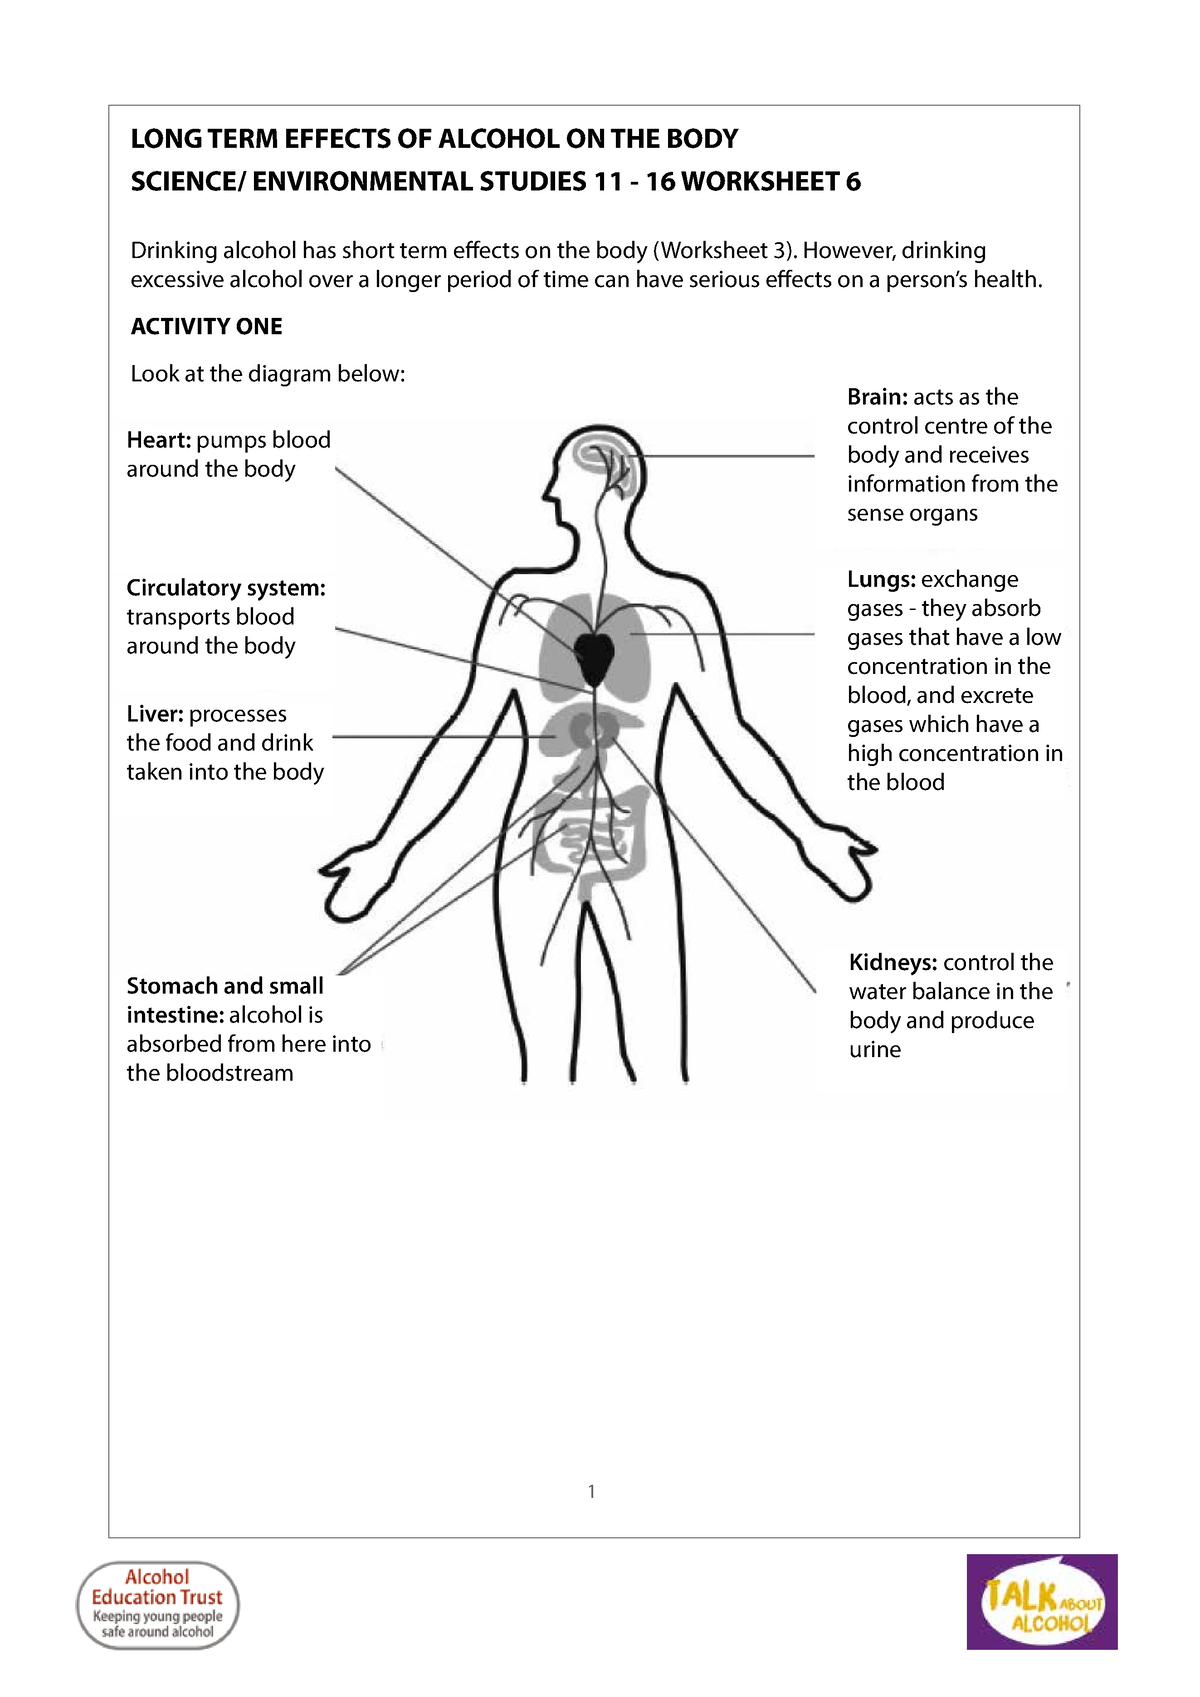

What Are The Long term Effects Of Fetal Alcohol Syndrome A Review By

Alcohol Long Term Effects SECTION 3 ALCOHOL AND ITS EFFECTS PHYSICAL

Alcohol Long Term Effects SECTION 3 ALCOHOL AND ITS EFFECTS PHYSICAL